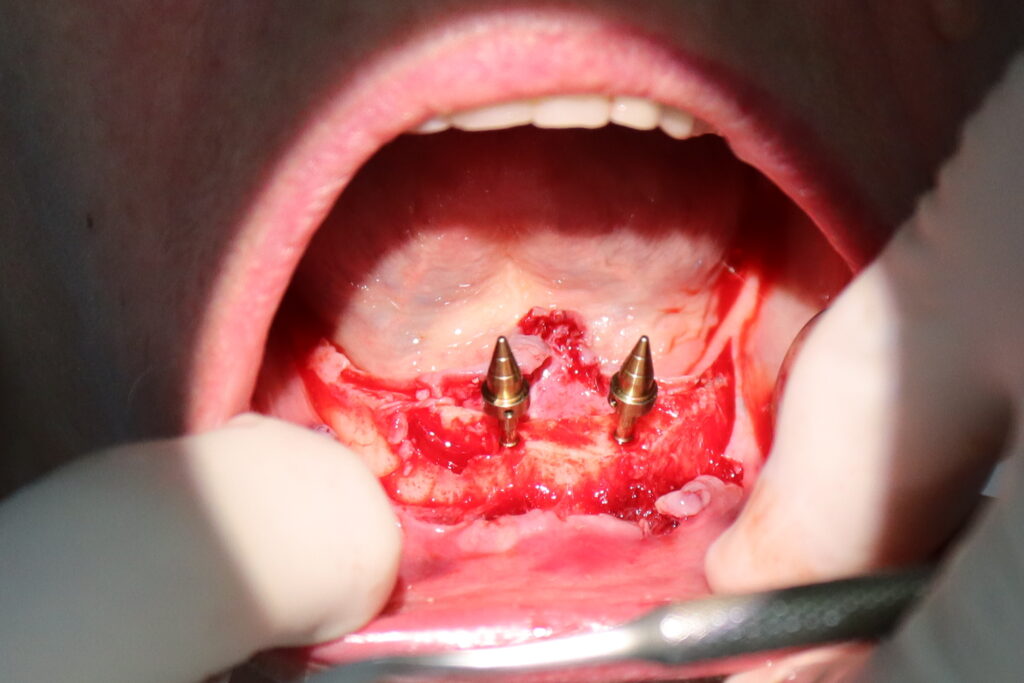

На верхней и нижней челюстях были удалены зубы и проведена комплексная имплантация по системе All-on-4, установлены 8 имплантатов Osstem.

процесс имплантации

Это фото может содержать тяжелый для восприятия контент